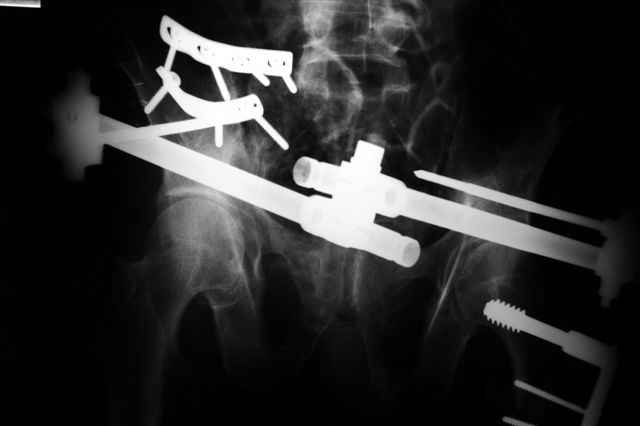

В приложении отправляю послеопер. снимки бедра и лодыжки обсуждаемого вчера больного.

Вчера прооперировал больного.

Попытка низвести половину таза на тракционном столе ( скелетное вытяжение за бедро) безуспешная.

из переднего доступа добрался до правого КП сочленения , все запаяно костью, с помощью 2 шанцев винтов в крестец и подвздошную кость и элеватора репозиция, контроль ЭОП

и двумя пластинами фиксация.

Спереди, аппарат как рекомендовал Джолдас.

Снимки плохого качества( очень темные) завтра переделают и пришлю на конференцию.

На мой взгляд, смещение устранено и фиксация выглядит вполне анатомичной.

В приложении послеоперационные картинки.